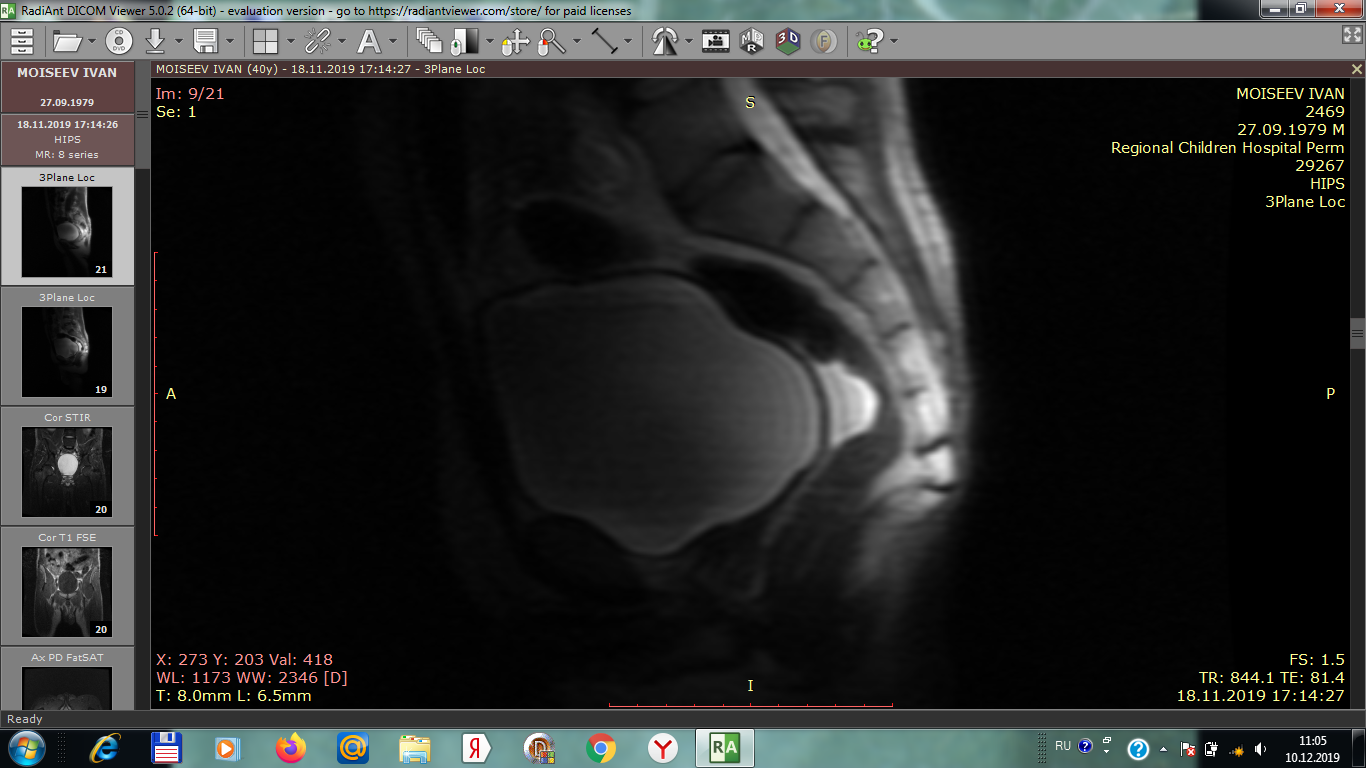

на мрт тазобедренного сустава обнаруженно .серацеле или киста в районе мюллерового протока , достаточно большая , никто до конца не может сказать что это